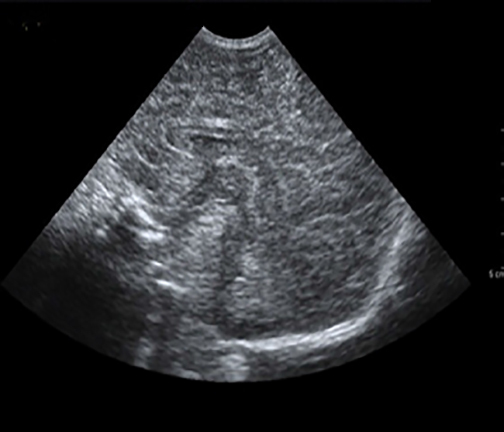

Neonatology Homogeneous Brain 3 Image